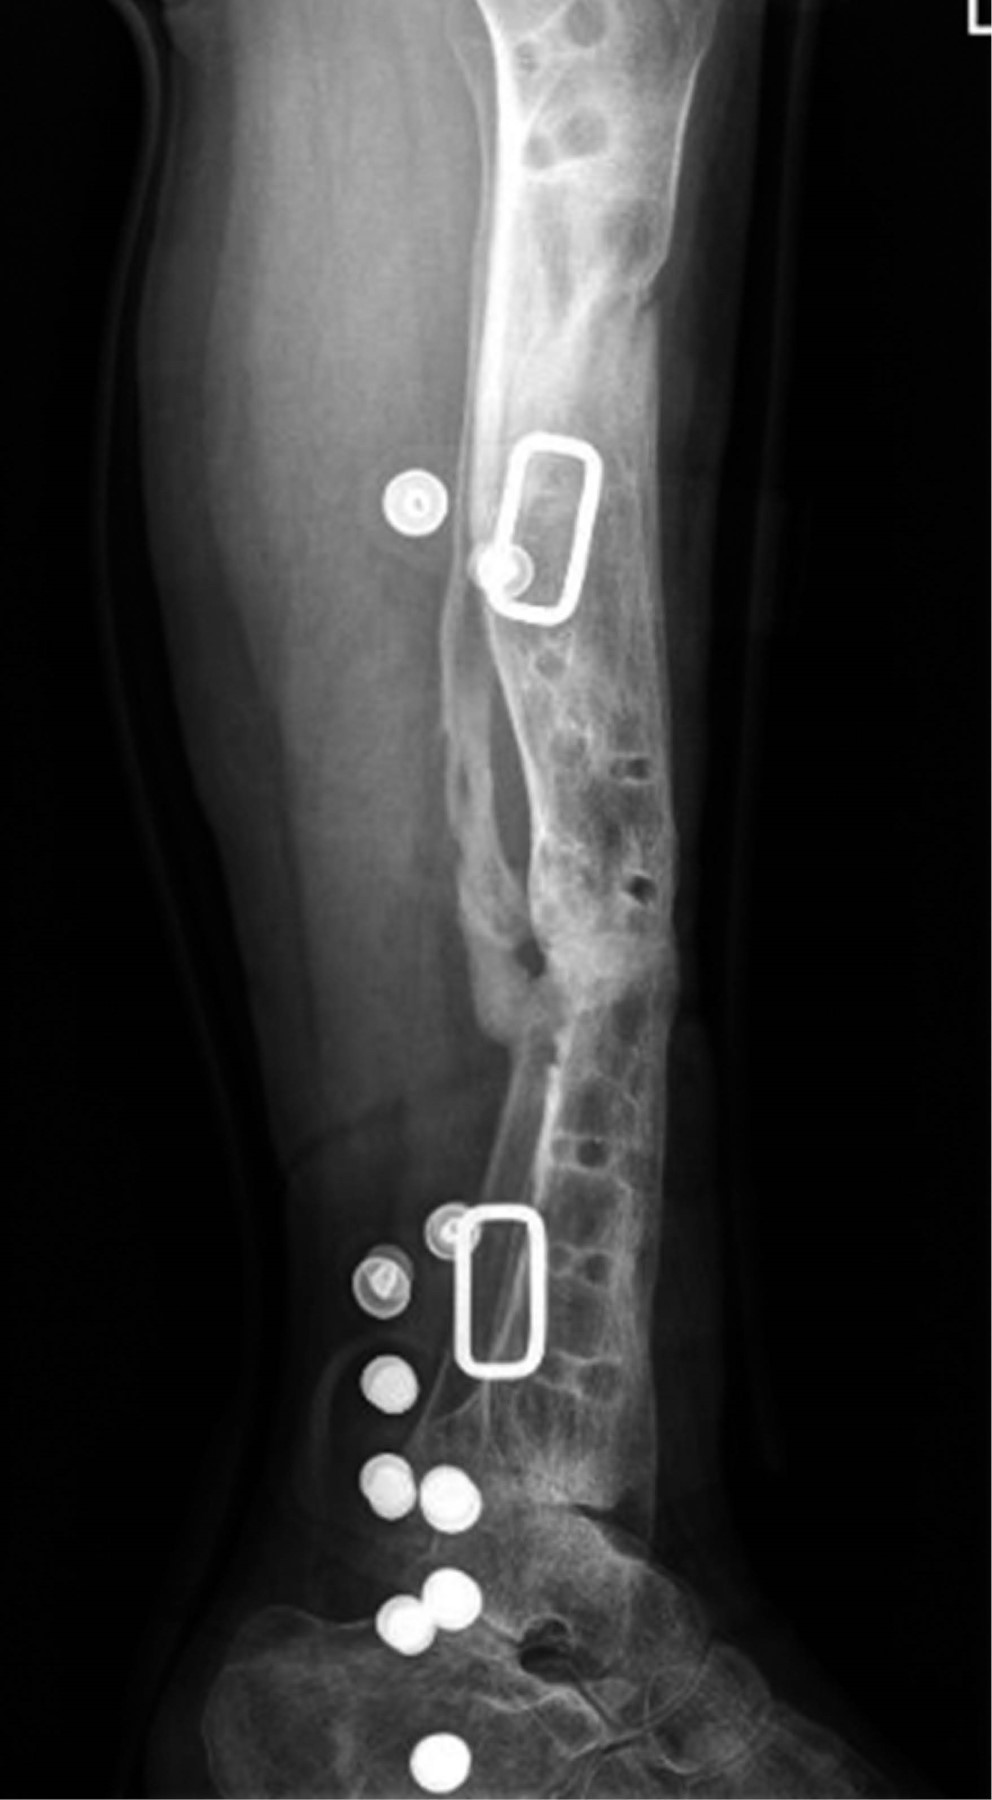

El método de De Bastiani consiste en la estabilización de los fragmentos comprometidos con tornillos troncocónicos no transfictivos, los cuales se fijan a un riel rígido con tres cabezales deslizantes (sistema de fijación externa tipo monorriel).2 Con el paciente en decúbito dorsal bajo bloqueo subaracnoideo en mesa radiolúcida y con intensificador de imágenes, se determinan líneas paralelas a la superficie articular, se colocan tres cabezales provisionales en regleta de elongador, se coloca un primer tornillo en cabezal proximal paralelo a articulación de rodilla, el segundo tornillo en cabezal distal paralelo a articulación de tobillo y un tercer tornillo en cabezal intermedio paralelo a la diáfisis de la tibia, después se colocan los tornillos restantes, quedando tres tornillos por cabezal, se cambian cabezales provisionales por los definitivos (Figura 3). Después se realiza incisión de 1 a 1.5 cm en la región proximal o distal según el sitio seleccionado para la corticotomía hasta periostio, se incide éste de manera longitudinal y se procede a perforar agujeros en las caras anteromedial y anterolateral del hueso para perforar la cortical posterior con broca 3.2 mm, mismos que se realizan con la menor distancia entre sí. A continuación, los agujeros se unen con un osteótomo una vez completada la osteotomía, porque la parte posterior se rompe de manera espontánea debido a la tensión aplicada antes del montaje. Se separan los segmentos mediante el distractor para asegurar que la osteotomía es completa y se confirma con el intensificador de imágenes. Se vuelven a aproximar los segmentos a distraer, sometiéndolos a una compresión leve y se aprietan las tuercas de bloqueo. Se cierra el periostio y la herida sin dejar drenajes. Se entrena al paciente y familiares sobre cómo realizar la distracción, cuándo iniciarla, frecuencia y sentido de la vuelta de la unidad de compresión-distracción, se le recomienda al paciente anotar en un cuaderno hora y fecha de distracción y sus observaciones como sensación de tracción, dolor o cualquier eventualidad. De no existir contraindicación alguna, se egresa al segundo día del postoperatorio. La fase de reposo dura en promedio 10 días. La distracción se realiza a razón de 1 mm por día, girando cuatro veces al día un cuarto de vuelta en sentido antihorario la unidad de compresión-distracción (0.25 mm cada 6 horas). Este promedio de distracción se acelera temporalmente cuando se observa una osificación rápida, o se reduce si la osificación es lenta o el paciente padece dolor o contractura muscular. La distracción es vigilada mediante controles radiográficos. Se cita a los 10 días del postoperatorio para valorar las heridas, retirar los puntos y verificar que entendió cómo iniciar la distracción. Tres citas semanales al inicio y quincenales posteriormente con radiografías de control. La fase de reposo dura en promedio un día. La distracción se realiza a razón de 1 mm por día, girando cuatro veces al día un cuarto de vuelta en sentido antihorario la unidad de compresión-distracción (0.25 mm cada 6 horas). Este promedio de distracción se acelera temporalmente cuando se observa una osificación rápida, o se reduce si la osificación es lenta o el paciente padece dolor o contractura muscular. La distracción es vigilada mediante controles radiográficos. Se cita a los 10 días del postoperatorio para valorar las heridas, retirar los puntos y verificar que entendió cómo iniciar la distracción. Nueva cita a los 10 días con radiografía de control para valorar que la distracción se realiza de manera correcta. Se le recomienda la carga parcial de aproximadamente 15 kg. Después se cita cada 30-40 días con radiografías de control para comprobar que se produzca la osteogénesis, en cuyo caso se continúa la transportación. Si la densidad del neoformado es pobre pero uniforme, se suspende la distracción por una o dos semanas. Si el neoformado es irregular, se comprime el segmento uno o dos centímetros a la misma velocidad de la distracción hasta que el callo sea uniforme, a continuación se reinicia la transportación. Al final de la transportación, cuando hay contacto de los dos fragmentos, la radiografía debe mostrar un callo uniforme (Figura 4). Se bloquea el cabezal del alargador para mantener el hueso nuevo en neutralización estable, el compresor-distractor es entonces retirado. Cuando así se requiere, una nueva cirugía puede realizarse para reavivar los bordes de la zona de contacto y colocar injerto para acortar el tiempo de consolidación, el soporte de carga en esta fase de neutralización se incrementa gradualmente en función del grado de mineralización del neoformado. Cuando la radiografía demuestra que el segmento es uniformemente denso y opaco, se dinamiza el elongador aflojando la tuerca del cabezal proximal y se bloquean las del cabezal medio y distal. Una vez que se ha logrado la corticalización completa, se procede al retiro del elongador y los tornillos troncocónicos, se realiza en quirófano y bajo anestesia general endovenosa (Figura 5).

De acuerdo con los criterios de selección, fueron incluidos un total de dos pacientes con pérdida ósea de tibia y fémur por pseudoartrosis infectada que recibieron tratamiento mediante transportación ósea con la técnica de De Bastiani durante el periodo de estudio. Uno fue del sexo masculino (50%) y uno femenino (50%). La edad promedio fue de 16 años (rango de 15 a 17 años). Una de las pérdidas óseas (50%) se presentaron como secuelas de fracturas expuestas y una de fracturas cerradas (50%). La fractura expuesta fue en la tibia izquierda y la cerrada en la tibia izquierda. Una de las fracturas se reportó por causa espontánea, idiopática, la fractura expuesta por caída de una caja de camioneta. En la fractura expuesta, el tratamiento inicial consistió en desbridamiento y fijación externa, con reducción abierta, fijación interna con placa de compresión bloqueable (LCP) 3.5. Para la fractura cerrada de tibia en reducción abierta fijación interna con placa LCP 3.5. Sólo un paciente no comenzó su tratamiento quirúrgico en este hospital (fractura cerrada de tibia) llegado a la consulta externa con placa fatigada y en pseudoartrosis infectada. La longitud de pérdida ósea promedio fue de 10 cm (rango de 7 a 11 cm). El sitio de la corticotomía en los dos casos fue diafisario proximal. La transportación ósea se inició en promedio con los 15 días después de la corticotomía (rango de 10 a 15 días). A los dos pacientes se les realizó técnica Masquelet durante el procedimiento. La velocidad de distracción promedio fue de 0.85 mm/día (rango de 0.57 a 0.98 mm/día). El tiempo de consolidación y corticalización del segmento transportado fue de 14.5 meses (rango de 6 a 22 meses), sólo en un caso fue de tres años (el caso de la fractura expuesta). El índice de corticalización promedio fue de 1.9 cm/mes (rango de 0.8 a 3.2 cm/mes). Los pacientes lograron la consolidación del segmento transportado aunque uno de los casos aún continúa con el fijador monorriel. Dos pacientes presentaron deformidad residual del segmento transportado, uno con retroverso de 6o y valgo de 5o; el segundo presentó anteverso de 15o. Discrepancia de las extremidades inferiores ocurrió en los dos pacientes, de 1.5, 2 cm y 2 cm. De acuerdo con el sistema de clasificación de Paley, dos pacientes tuvieron resultados óseos excelentes (71%) y uno buenos (29%) (Tabla 2).

Tal y como se realizó en el presente estudio, el inicio de la transportación ósea posterior a la corticotomía se recomienda entre los primeros siete a 15 días, ya que si se inicia en forma previa el neoformado no es de calidad adecuada y se fractura; después de 15 días la corticotomía consolida y es difícil iniciar la transportación. La velocidad de distracción recomendada es de ¼ vuelta al día, y el índice de corticalización reportado en la bibliografía es de 1 cm/mes en niños y de 2 a 3 cm/mes en adultos. Los resultados óseos y funcionales obtenidos en nuestro estudio son muy similares a los reportados por Paley y Tucker, quienes realizan este procedimiento. Una de las principales complicaciones encontradas durante la transportación ósea fue el proceso infeccioso, el cual estuvo siendo valorado por el Servicio de Infectología con antibioticoterapia basada en los cultivos. El dolor durante la transportación ósea es una complicación esperada secundaria a la distracción de los tejidos blandos, en esta evaluación, un paciente refirió dolor leve, el cual cedía a analgésicos orales; cuando la sintomatología no cede, es posible detener la distracción por un breve periodo, rehabilitar movilizando las articulaciones próximas y reiniciar posteriormente la distracción. Ningún caso presentó fractura durante el proceso; la fractura del neoformado es una de las complicaciones que pueden presentarse, según lo reportado por Aronson y Tucker.6 De acuerdo con nuestros resultados, consideramos que la transportación ósea es una buena alternativa en el manejo de las pérdidas óseas mayores de tibia, por lo que recomendamos su uso en casos de pérdidas importantes.7 Sin embargo, debe considerarse que durante el seguimiento pueden presentarse algunas complicaciones o dificultades técnicas, por lo que este procedimiento debe realizarse por cirujanos con un entrenamiento adecuado (Figura 6).

Figura 5